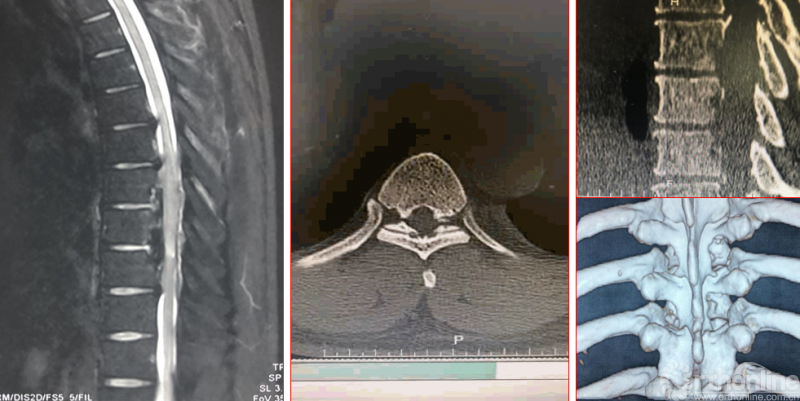

术前资料